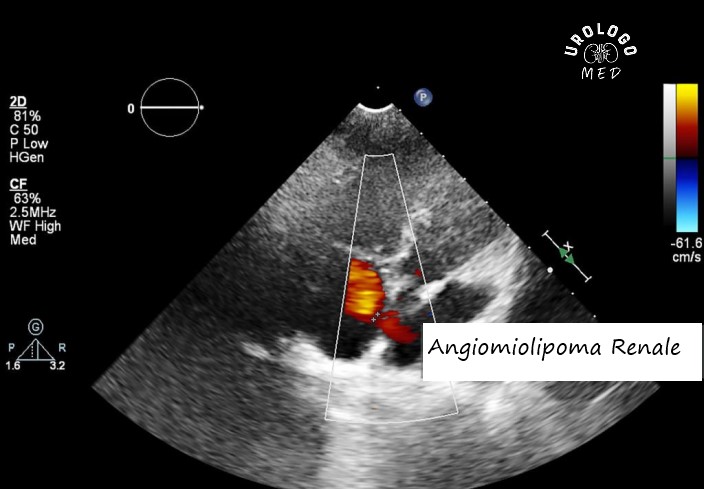

Metodi di Visualizzazione

Per diagnosticare l'angiomiolipoma renale si utilizzano l'ecografia (US), la tomografia computerizzata (TC) e la risonanza magnetica per immagini (RMI). L'ecografia è il primo passo: è poco costosa, innocua e rivela il tessuto adiposo di un tumore in 15-20 minuti, ma può tralasciare piccoli dettagli. La TC è il gold standard, poiché mostra dimensioni, struttura e vasi con precisione millimetrica, anche se le radiazioni la rendono meno adatta per un uso frequente. La risonanza magnetica è ideale per i casi complessi: senza radiazioni, mostra i tessuti molli in dettaglio, ma richiede 30-40 minuti di immobilità, il che non è adatto a tutti.

Come scegliere un metodo? Se un'ecografia ha rilevato un angiomiolipoma fino a 4 cm senza sintomi, è sufficiente ripeterla una volta all'anno. Se si sospetta un'emorragia o una crescita, la TC fornirà una risposta rapida, mentre la RM sarà utile in caso di allergia al mezzo di contrasto della TC. È utile che i pazienti verifichino in anticipo con il proprio medico quale sia il metodo più adatto al loro caso, per evitare costi e stress inutili: questo è il primo passo per decidere quando rimuovere il tumore.

L’Importanza della Componente Grassa nell’Angiomiolipoma Renale

La caratteristica principale dell'angiomiolipoma renale è la presenza di grasso, che lo distingue dai tumori maligni come l'adenocarcinoma. Nell'ecografia, il grasso appare come punti luminosi, nella TC come aree di bassa densità (da -20 a -80 unità Hounsfield) e nella RM come segnali soppressi da modalità speciali. Se c'è molto grasso, la diagnosi è chiara e questo è rassicurante: il cancro non ha questo aspetto. Ma nel 5-10% dei casi lo strato di grasso è sottile, il che rende il tumore potenzialmente pericoloso e richiede ulteriori esami.

Ciò è di importanza pratica: la componente grassa sottile potrebbe richiedere un test genetico per la sclerosi tuberosa, soprattutto nei pazienti giovani. Se la diagnosi è dubbia, i medici raccomandano un controllo dopo 3-6 mesi, anziché un intervento chirurgico immediato. I pazienti dovrebbero chiedere in che modo il grasso influisce sulla loro prognosi e non aver paura di chiedere se vengono suggerite procedure non necessarie: questo li aiuta a capire quanto sia pericolosa la situazione e quando è necessario intervenire.